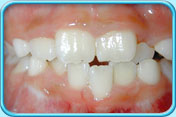

牙齒蛀壞

牙科醫生把牙齒蛀壞的部分清除,然後填上補牙物料。